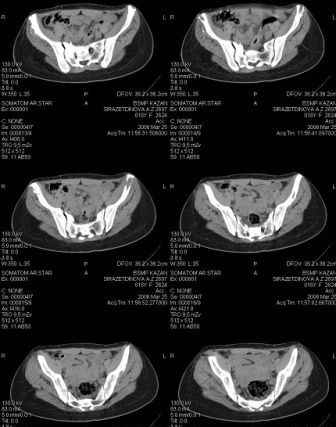

Предоставляю срезы. Если пациентку функционально ничего не беспокоит, стоит ли навязывать ей лечение.